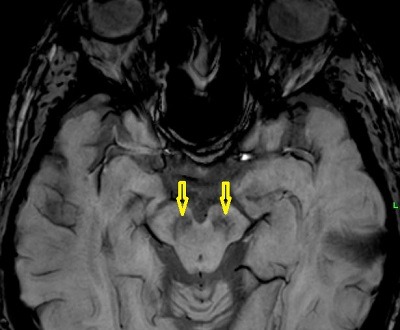

Hirtelen szívmegállás? Rák? Sokak által rettegett betegségek. Azonban van még ezeknél is kegyetlenebb: ilyen az Alzheimer kór, a felejtés betegsége, mikor az ember előbb csak a szavakat nem találja, aztán már a szeretteit sem ismeri fel, de nem képes már a WC-re sem kimenni. A másik kór, mellyel hosszú évekig kínlódnak az emberek, mielőtt meghalnak: a Parkinson....